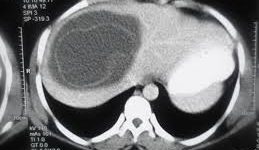

این بیماری یه بیماری انگلی است که از سگ و به واسطه مصرف گوشت الوده گوسفند ممکنه به انسان منتقل بشه . بیشتر داخل کبد و ریه قرار میگیره و رشد میکنه . فرد مبتلا ممکنه مدتها بدون علامت باشه ولی وقتی بزرگ بشه درد ایجاد میکنه . تشخیص با سونوگرافی هست .تست از طریق خون هم کمک میکنه .

وقتی تشخیص داده شد باید ریه هم بررسی بشه که کیست نداشته باشه. درمانش اکثرا در حالتی که کیست زنده است اینه که جراحی بشه و کیست تخلیه بشه. این عمل به صورت باز و یا لاپاراسکوپیک قابل انجام هست . مصرف آلبندازول قبل و بعد عمل کمک کننده است .